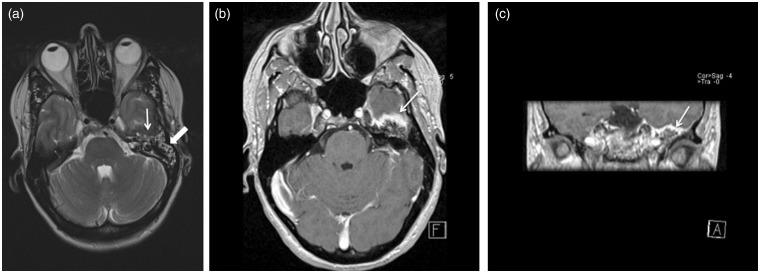

我们报告一例颞骨脑膜瘤延伸到中耳腔,临床表现为浆液性中耳炎的影像特征。颞骨脑膜瘤延伸至乳突或中耳腔,是非常罕见的。如果原因不明或治疗抵抗浆液性中耳炎和鼻咽肿瘤被排除,应进行颞骨计算机断层扫描(CT)。如果CT表现提示颞骨脑膜瘤,则磁共振成像(MRI)加钆检查将确认诊断并显示病变的确切范围。

We report the imaging features of a case of a temporal bone meningioma extending into the middle ear cavity and clinically presenting as a serous otitis media. Temporal bone meningioma extending in the mastoid or the middle ear cavity, however, is very rare. In case of unexplained or therapy-resistant serous otitis media and a nasopharyngeal tumor being ruled out, a temporal bone computed tomography (CT) should be performed. If CT findings are suggestive of a temporal bone meningioma, a magnetic resonance imaging (MRI) examination with gadolinium will confirm diagnosis and show the exact extension of the lesion.